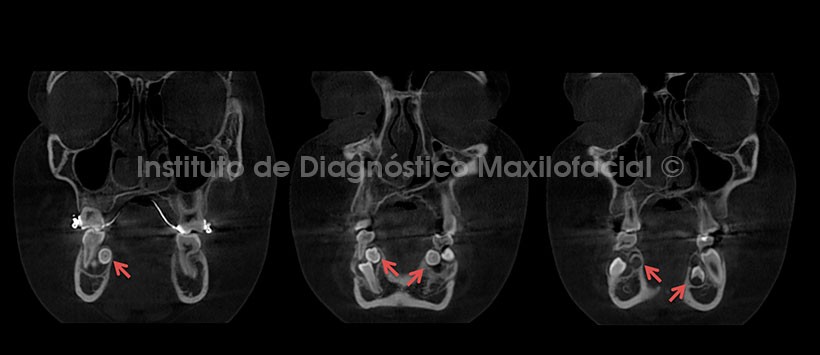

A la evaluación de la tomografía volumétrica (CBCT) en cortes axiales (Figura 2), coronales (Figura 3) y sagitales (Figura 4), se observan los folículos antes descritos en evolución intraósea, con proximidad hacia la tabla ósea lingual, sin causar alteración de las estructuras adyacentes.